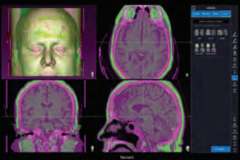

Navient ENT

NaviENT didesain agar tidak menghabiskan banyak menyita banyak tempat di sekitar meja operasi yang sudah sesak. Single Cart, ringkas, langsing, dapat dilipat, dan mudah didorong hingga ke dekat lokasi prosedur. NaviENT juga dengan mudah disimpan sesudah prosedur selesai.

Navient didesain fokus pada hal-hal esensial:

1.Mudah dan segera siap dipakai. SET UP CEPAT HANYA 5 MENIT

2.Akurat, akurasi hingga 0,2 mm

3.Biaya operasional yang sangat rendah. TIDAK MEMERLUKAN CONSUMABLE

4. Instrument dengan permanent marker yang dapat disteril. TIDAK DIPERLUKAN KALIBRASI INSTRUMEN SETIAP KALI PAKAI

5.Hemat ruang.